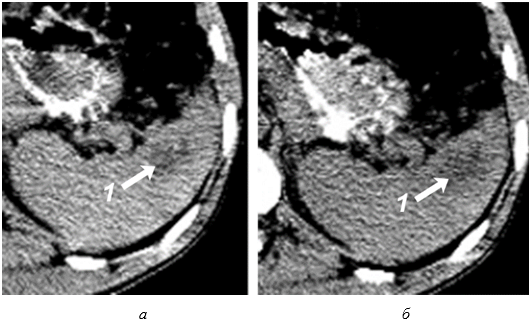

Необходимо указать, что при первичном исследовании (3–5 часов после травмы) ни в одном наблюдении не представилось возможности достоверно выявить подкапсульный разрыв селезенки в виде эхонегативной зоны. Повреждения визуализировались как нечетко очерченные участки паренхимы с незначительно сниженной эхогенностью, имевшие «смазанную» структуру, нехарактерную для паренхимы селезенки (рис 3).

Рис. 3. Эхограмма подкапсульного разрыва селезенки (3–5 часов после травмы). Зона повреждения указана стрелками.

Сканирование селезенки через 8–12 часов после травмы позволяет выявить прогрессирующее неравномерное снижение акустической плотности в зоне интереса (рис. 4, а). Устойчивая визуализация эхонегативной зоны (внутритканевой гематомы) становится возможной по истечении первых суток посттравматического периода (рис. 4, б).

Рис. 4. Эхограмма подкапсульного разрыва селезенки: а – через 8–12 часов после травмы; б – через 1 сутки после травмы.